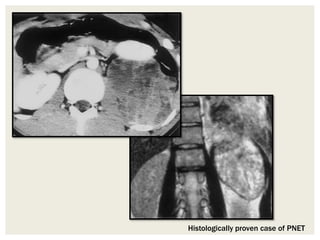

Small Round Cells

• Lymphomas are the most commonly encountered tumors

composed of small round cells.

• They are homogeneous, with minimal contrast enhancement

at CT and relatively low signal intensity at T2-weighted MR

imaging representing densely packed cellular components.

• An exception is primitive neuroectodermal tumor (PNET),

which often appears heterogeneous at MR imaging

Histologically proven case of PNET